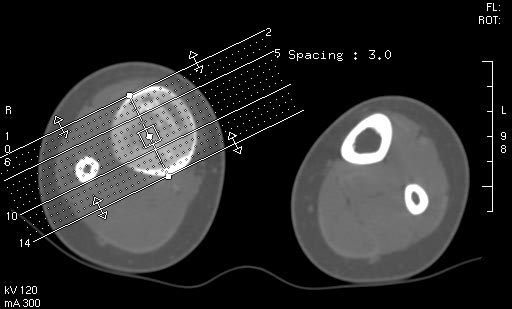

胫骨中段皮质内环绕并突入髓腔膨胀性生长的软组织密度病灶,内缘粗糙,外缘光滑无中断,病灶内可见小点状钙化.未见骨膜反应及瘤骨;软组织显示如常,未见肿块及异常密度.

右胫骨中段囊性、膨胀性改变,病变呈中心性,沿骨的纵轴生长,病变区骨皮质明显变薄,骨包壳完整,无中断,病变边缘无明显硬化,未见明显骨膜反应,周围软组织无肿胀。首先肯定的是骨良性病变(良性骨肿瘤或肿瘤样病变。有以下几种可能:

1 骨囊肿:发生于骨干的囊肿,可沿髓腔的长轴发展,在髓腔形成长囊状骨折破坏区,但骨囊肿病变周围一般都有明显边缘硬化,易发生病理性骨折,这点不支持。

2 动脉瘤样骨囊肿:好发于长骨干骺端,多偏心生长于骨干的一侧,易多囊、分隔、有嵴(皂泡样),中心型可沿纵轴生长,呈溶骨性囊样,但囊内也多含粗或细的骨小梁,边缘也有硬化环包绕。也不太支持。

4 骨巨细胞瘤:好发于骨端,偏心性向骨的横轴生长多见,呈皂泡样,但也有较少见的发生于骨干的呈中心性生长的巨细胞瘤,破坏边缘无明显硬化边,此点符合。

5 骨纤维异常增殖症:可有囊状膨胀性、磨玻璃样、丝瓜瓤样及虫蚀状多种表现,囊状膨胀性可有类似改变,但范围一般较广,也常绕硬化环。

总之,我感觉骨肿瘤及肿瘤样变鉴别诊断很困难,有时病变表现不典型时影像很难确诊,此病例我的诊断是:骨巨细胞瘤>骨血管瘤>骨纤。